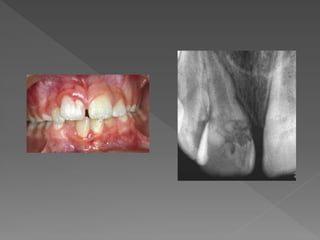

 Clinical evaluation-

 Generally asymptomatic

 The process of resorption is active only if part of the

pulp remains vital; therefore, pulp testing can be

positive. However, usually the coronal pulp is necrotic

while the apical pulp is vital, resulting in a

nonresponsive test.

 Pain may be present if perforafion of the crown or root

occurs.

 If resorption takes place in the coronal portion of the

tooth, the tooth may exhibit a pinkish or reddish hue

because of the presence of numerous capillaries in

the pulpal granulation tissue undermining the coronal

enamel and this is called as pink tooth of mummery.

 Radiographic evaluation – It appears as a

circumscribed, oval enlargment (radiolucency)

continuous with the root canal.

 Treatment –

 Nonsurgical root canal therapy is

recommended. Treatment generally

consists of the preparation of the

canal to the apical foramen with

particular emphasis on irrigation and

ultrasonic activation of iirigants so that

the resorbed area is cleansed as

thoroughly as feasible.

 The obturation of the canal can be

achieved by a variety of techniques

including hot vertically condensed

gutta-percha, thermoplasticized gutta-

percha.

 Failure to treat internal inflammatory

resorption can lead to its eventual

extension to the periodontal ligament,

via a crown or root perforation. In

these cases, a periodontal procedure,

such as crown lengthening or root

extrusion, may be implemented to

gain access for repair.